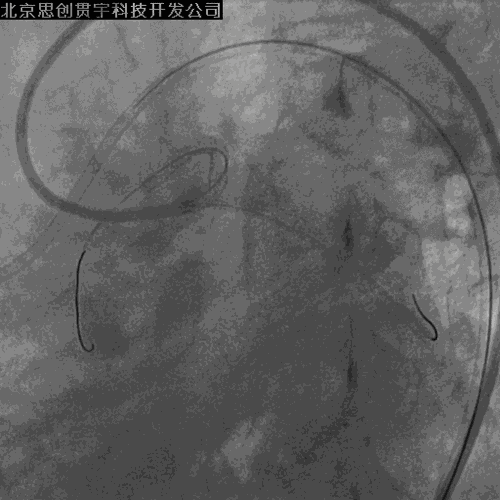

LCX开口狭窄

Finecross及双腔微导管支持下,

导丝均无法穿LM-LAD支架网眼至LCX

再次逆向掏LCX网眼

穿微导管技术( Modified Rendezvous )